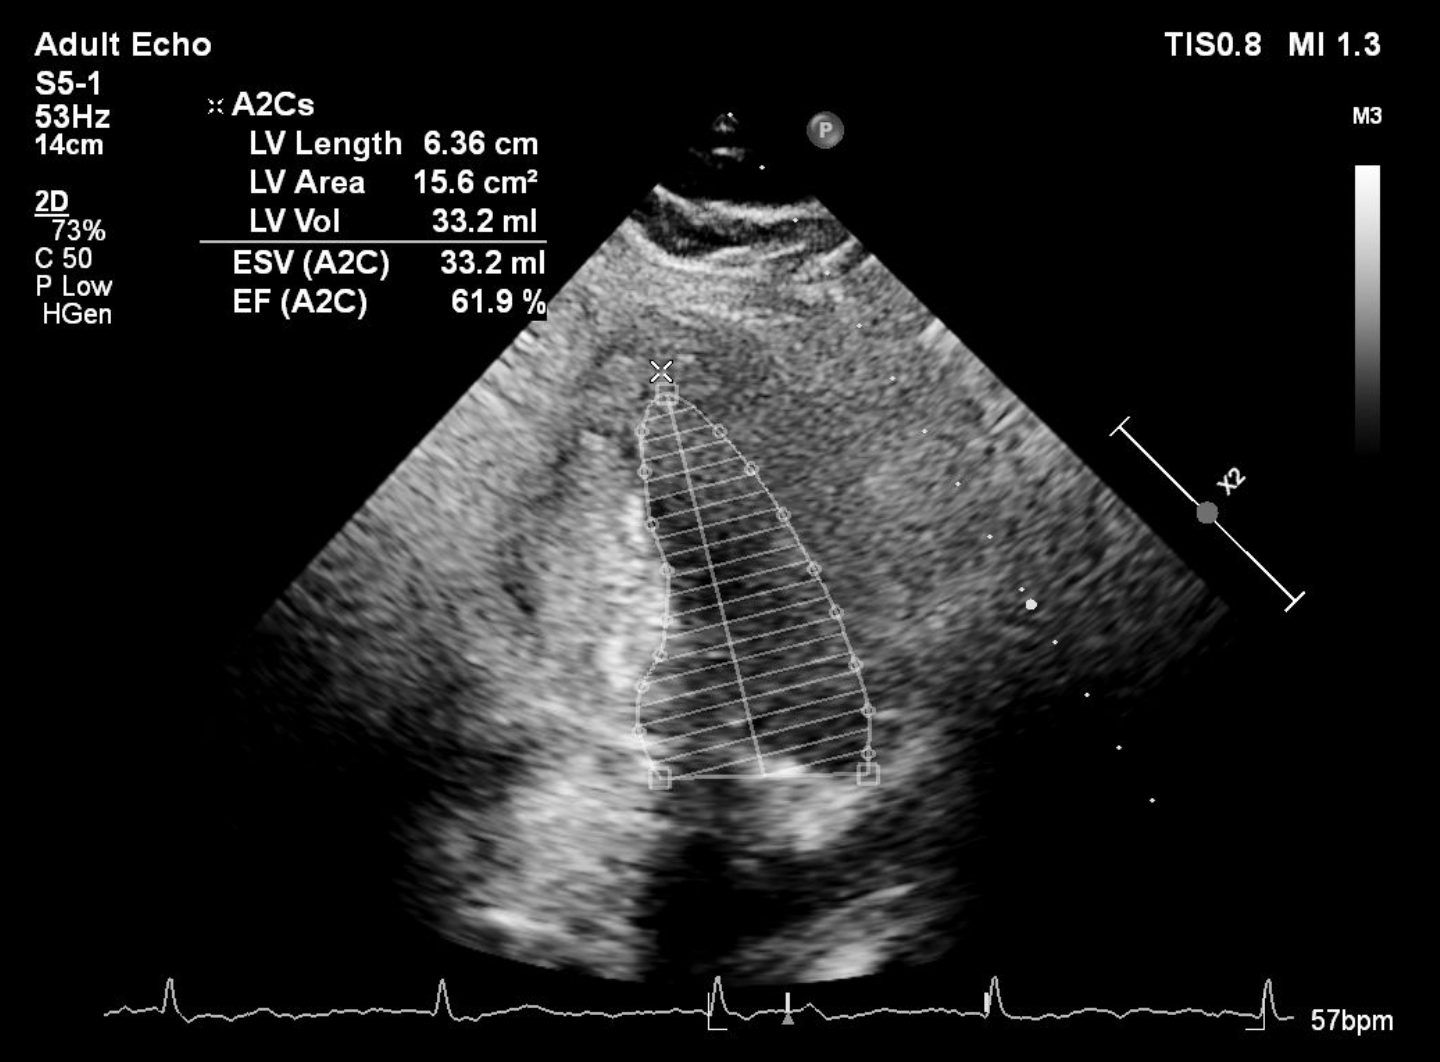

Resting ECG was normal. Referring hospital¡¯s treadmill test showed positive ischemic response with high-risk Duke score. Echocardiography showed preserved ejection fraction.

Angiography showed small non-dominant RCA with proximal severe stenosis, Left Main with severe tubular calcified stenosis at distal segmen, bifurcation lesion (medina1-1-1), LAD with diffuse calcified subtotal stenosis from ostial–mid, and LCX iwth severe tubular calcified stenosis at ostial.